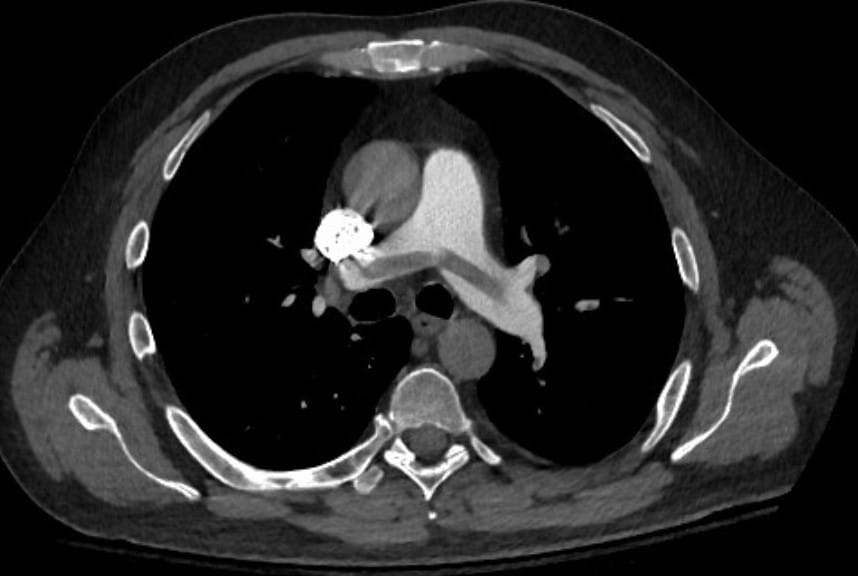

There are basically two schools of thought in this regard. The first, is that patients should only undergo routine screening as per age and gender recommendations for the general population. This usually means a thorough history and physical examination and basic laboratory testing and sometime a chest X ray. Depending on the patient’s age and gender PSA testing, colonoscopy and mammogram may be added. A second approach is to add specialized testing if the above testing failed to secure a diagnosis. This generally means adding an abdomen pelvis contrast enhanced computed tomography or similar test.

A systematic review was published in the annals of internal medicine in 2008. It compared data regarding limited versus thorough cancer screening for patients presenting with venous thromboembolism. Patients had both provoked and unprovoked events. A total of 14 studies were included in the analysis. The primary outcome was new cancer diagnosis. The main result of this paper was that more extensive evaluation resulted in more cancer diagnosis. Only computed tomogrpahy seemed to add real value while other modes of extensive screening (such as tumor markers or abdominal ultrasound) did not reach significance. Patient outcome measures were not studied. Thus, this paper could not comment about whether or not finding cancer was better or not for patients.